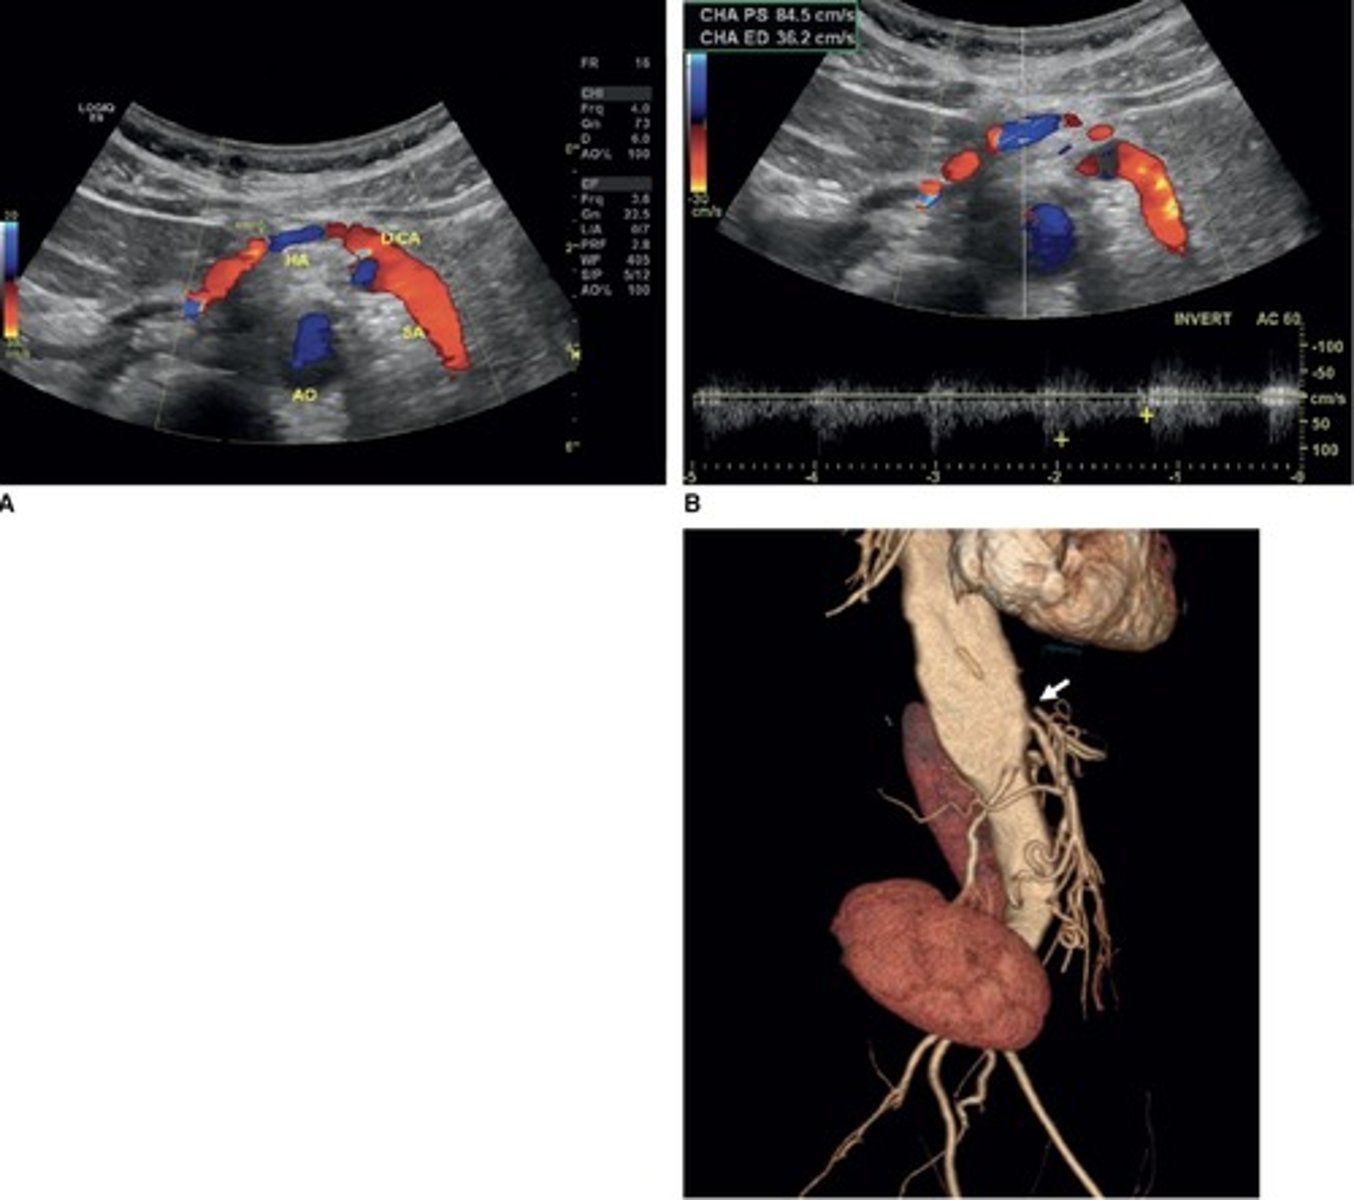

Replaced Right Hepatic Artery

Right hepatic artery branches off something else besides celiac artery - usually SMA

Common Trunk Variant

Celiac and SMA come off common trunk